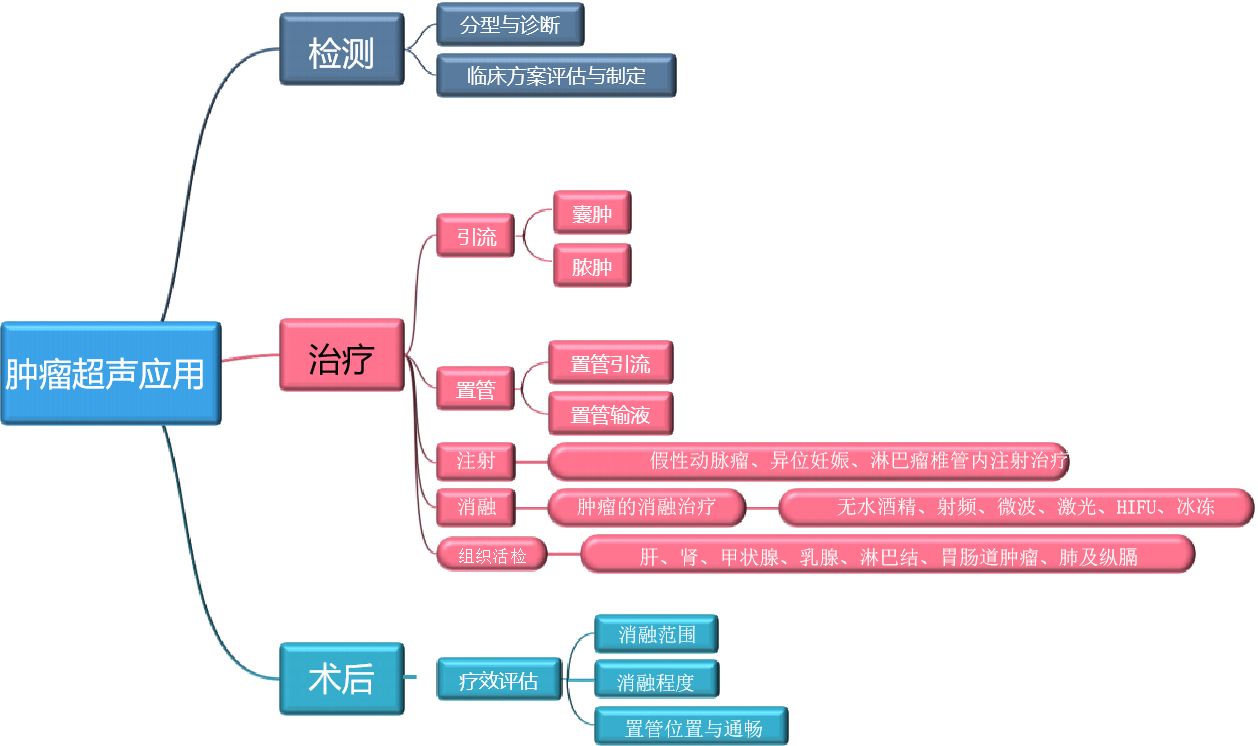

肿瘤的临床解决方案

3377体育医疗肿瘤相关的技术介绍

??平面波超快速成像平台??平面波超微细血流显像??实时剪切波弹性成像??多模态复合成像??声速定量成像??超声造影??智能介入整体解决方案